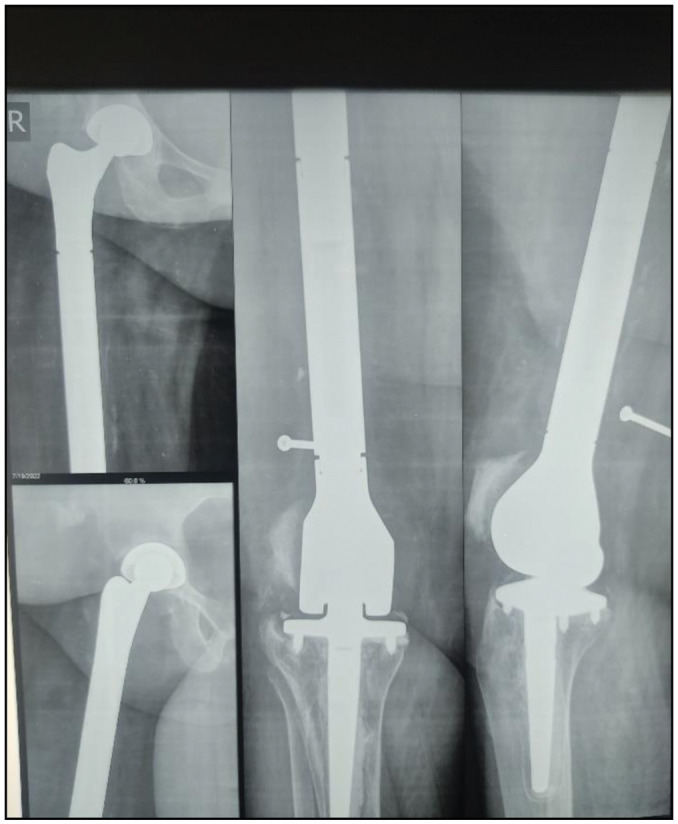

全股置换术(TFR)不是一种常见的手术,大多数指征是肿瘤病理。然而,很少有非肿瘤适应症可能需要TFR;这可能是对先前髋关节和/或膝关节手术失败导致股骨骨丢失的一种挽救性手术。我们报告一位59岁的肥胖女性,右大腿疼痛,行走困难5年。10年前,由于严重的膝骨关节炎,她接受了双侧全膝关节置换术。患者在发病前3年跌倒,右膝周围假体周围骨折,采用固定角度钢板和螺钉进行治疗。这是复杂的种植体断裂和不愈合。随后,她在发病前2年进行了植入物移除和右股骨远端置换术(DFR)。DFR手术一年后,她开始经历“启动”疼痛,膝盖周围不稳定,在没有支撑的情况下行走困难。临床和放射学诊断为股骨远端大型假体无菌性松动,并提供翻修DFR手术,但由于骨水泥技术不佳,股骨近端骨质流失和严重骨质疏松症,该手术也失败了。病人最终接受了右侧全股骨置换手术来挽救肢体。随访12个月后,患者下肢功能评分为27分。TFR对于股骨严重受损和/或多次非肿瘤性股骨手术导致的严重骨丢失是一种可行的挽救性手术。

Total femoral replacement (TFR) is not a common surgery and most indications are for oncological pathologies. However, there are few instances where non-oncological indications might necessitate TFR; this may be a salvage surgery for failed previous hip and/or knee surgeries with consequent significant femur bone loss. We present a 59-year-old obese woman with right thigh pain and difficulty with walking of 5 years duration. She had undergone bilateral total knee replacement 10 years earlier on account of severe knee osteoarthritis. She had a fall 3 years prior to presentation and sustained a periprosthetic fracture around the right knee which was managed with a fixed angle blade plate and screws. This was complicated by implant breakage and non-union. She subsequently had implant removal and a right distal femur replacement (DFR) surgery 2 years prior to presentation. A year after the DFR surgery, she began to experience "start-up" pain, instability around the knee and difficulty with walking without support. A clinical and radiologic diagnosis of aseptic loosening of the distal femur megaprosthesis was made and she was offered a revision DFR surgery which also failed due to poor cementing technique, bone loss at the proximal femur, and severe osteoporosis. Patient ended up with a right total femur replacement to salvage the limb. She had improved Lower Extremity Functional Score of 27 after 12-month follow-up. TFR is a viable salvage procedure for severely compromised femur and/or significant bone loss from multiple non-oncological surgeries of the femur.